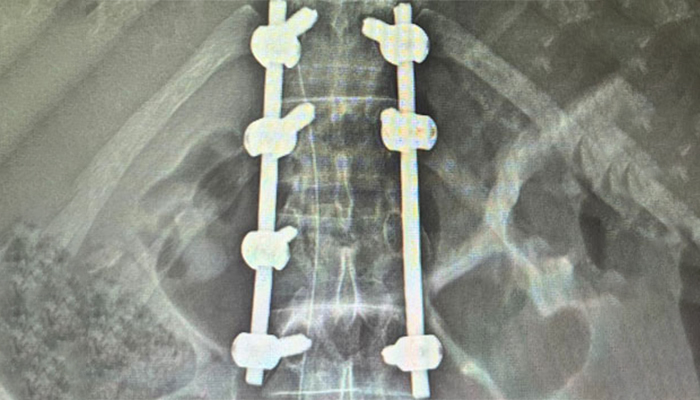

Management of Spine Trauma Fractures